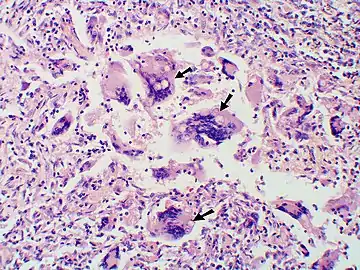

Granuloma with early suppuration. Fungal organisms difficult to recognize at this low magnification.

Large yeast-like fungi seen within giant cells at arrows.

Large yeast-like fungi seen within giant cells at arrows. Budding yeasts in cytoplasm of giant cells at arrows. Broad-based budding and double contoured cell wall seen in the giant cell in the center is characteristic of Blastomyces dermatitidis.